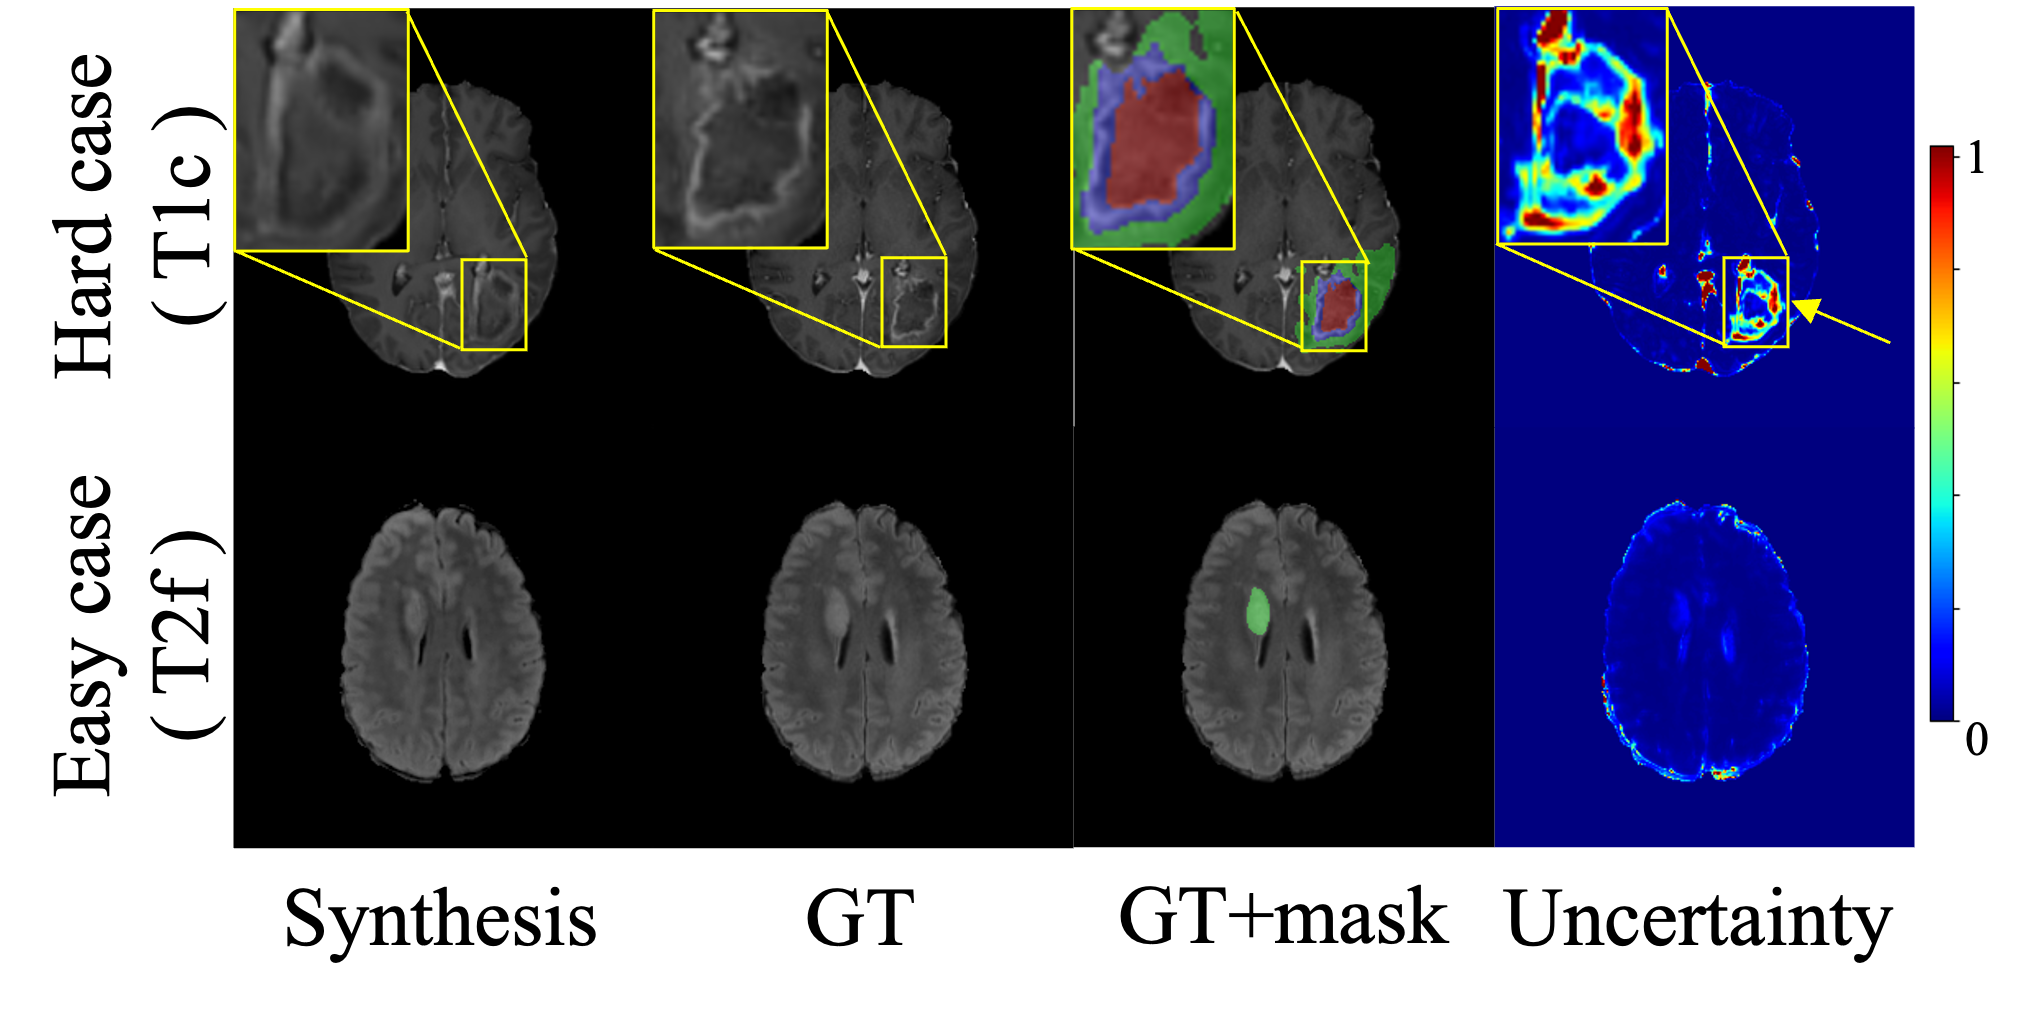

Refer to caption

Figure 4: Left: Reliability visualization assessment, where purple mask shows enhanced tumor region, green mask shows oedema region, and red mask shows necrotic core. Right: Ablation study results evaluated on BraTS-Africa dataset.

We conducted an ablation study to evaluate the effectiveness of our key components. As shown in the right of Fig. 4, MoNIG achieves lower UCE compared to Deep Ensemble [3], indicating more accurate uncertainty estimation. Through uncertainty-guided fusion, MoNIG further achieves higher-quality synthesis results. Furthermore, incorporating calibration on top of MoNIG leads to optimal performance in both image synthesis and uncertainty estimation, demonstrating the robustness of our MoNIG and calibration strategies.

Furthermore, the left of Fig. 4 demonstrates the reliability of our uncertainty estimation. We visualize uncertainty maps for hard and easy cases. In the first row (hard case), the yellow arrow indicates a risky region in the generated image, corresponding to the enhancing tumor area. This region shows high uncertainty as it is difficult to identify in T1n and T2w source images, correctly indicating potential errors. In contrast, the second row shows a case with lower uncertainty, suggesting a more reliable synthesis. Such uncertainty visualization can provide valuable guidance for clinical diagnosis by helping physicians identify regions requiring additional verification.